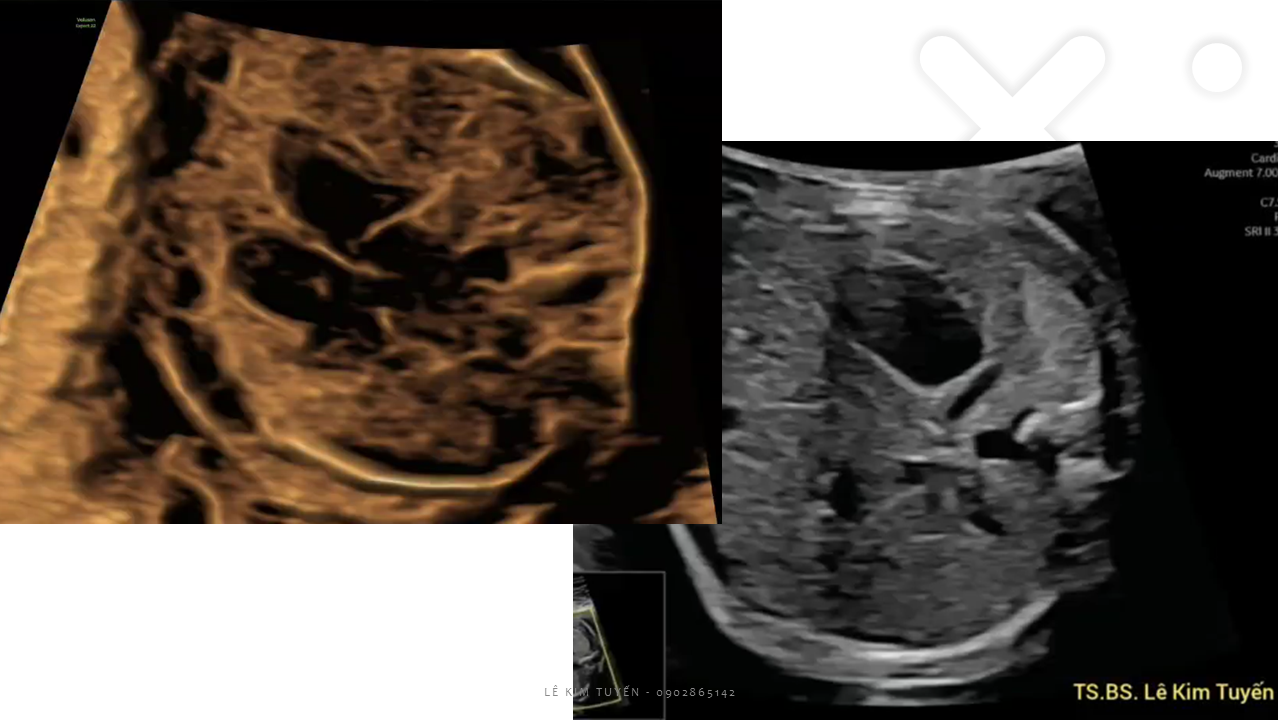

Siêu âm tim thai - Các kỹ thuật hiện đại

TS. BS. Lê Kim Tuyến

Bệnh viện Tim Tâm Đức